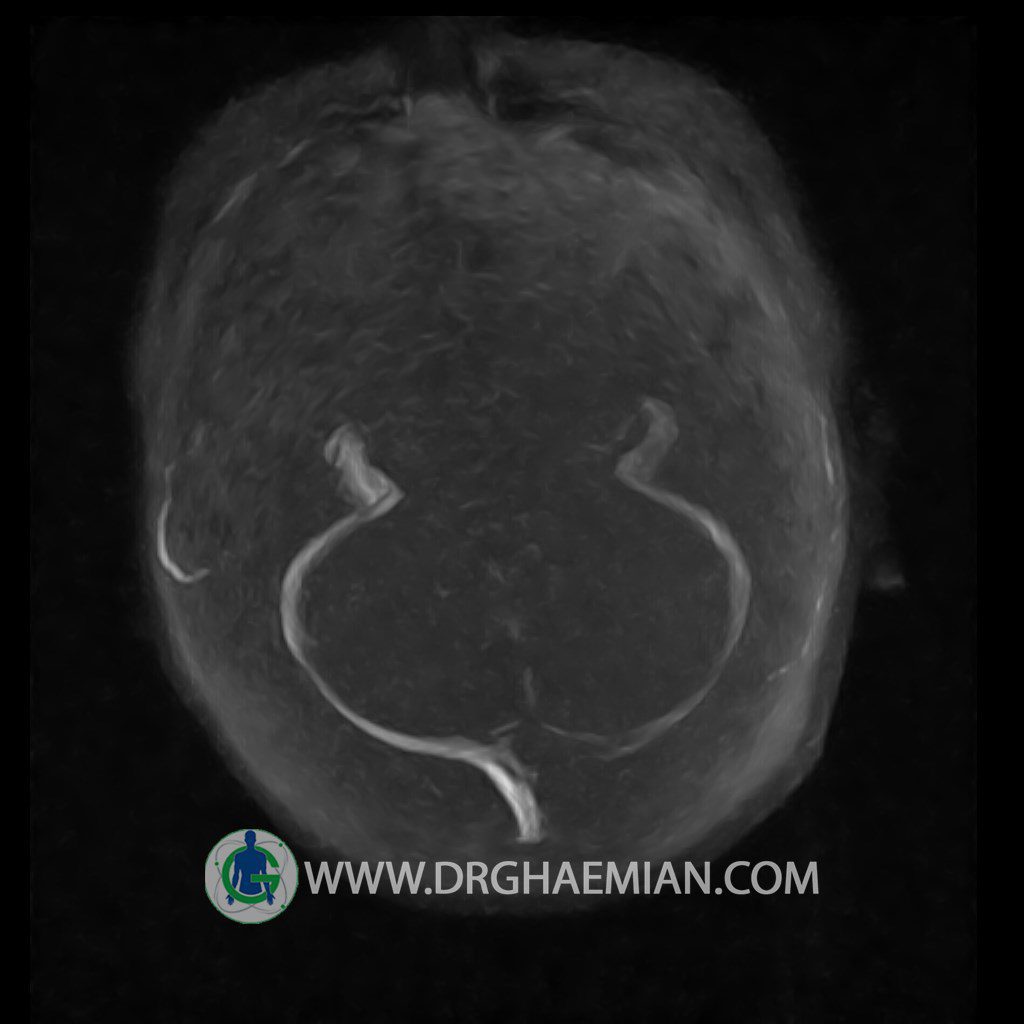

CRANIAL MRV

Technique: TOF ( time of flight ).

Images of the venous cranial vessels demonstrates a superior sagittal sinus of normal caliber with normal arrangement of draining superficial cerebral veins.

The great cerebral vein Galen inferior sagittal , straight sinus and left sigmoid sinuses appear normal.

The right transverse and sigmoid sinuses present a normal caliber.

– Narrowing of left transverse sinus without inthimal irregularity & without filling defect suggestive for cengenital hypoplasia